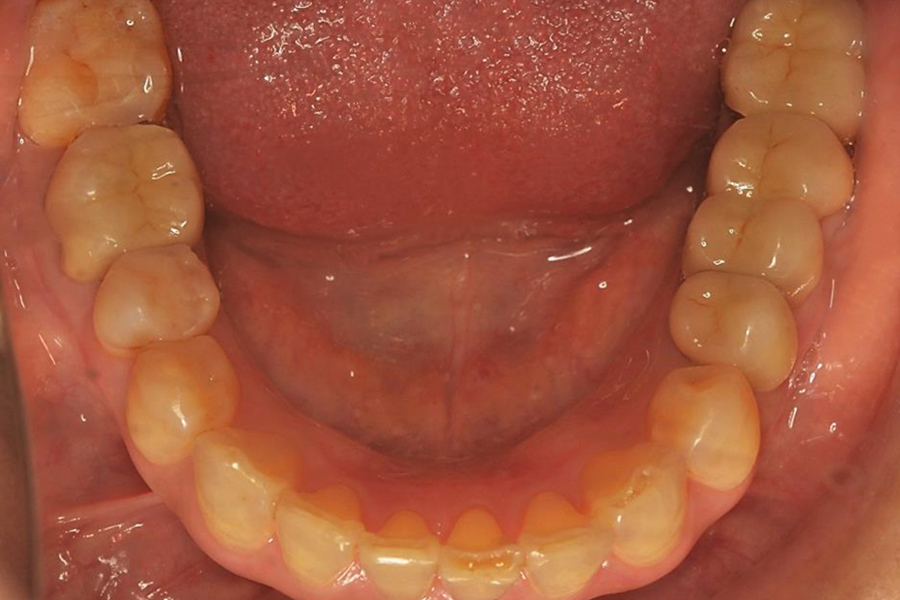

| 症状 | 奥歯のブリッジが取れてしまって食事がしにくい |

| 原因 | ブリッジ下の2次カリエス(虫歯の再発) 咬み合わせの不調和による咬合力の不均衡 |

| 治療法 | 矯正治療 自家歯牙移植 メタルボンドセラミッククラウン |